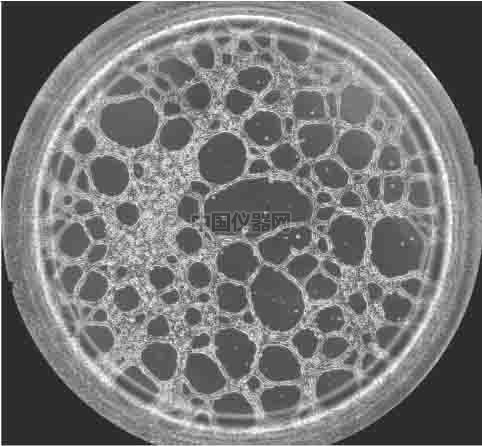

圖一 血管生成鏡檢圖 一.實驗材料和實驗方法 1.實驗材料

前言 無論原發(fā)性腫瘤還是繼發(fā)性腫瘤,一旦生長直徑超過1~2 mm,都會有血管生成。這是由于腫瘤細胞自身可分泌多種生長因子,誘導血管生成。多數(shù)惡性腫瘤的血管生成密集且生長迅速。因此,血管生成在腫瘤的發(fā)展轉(zhuǎn)移過程中起到重要作用,這一過程將能明顯阻止腫瘤組織的發(fā)展和擴散轉(zhuǎn)移。于是體外的血管生成實驗就能很好的模擬腫瘤的血管發(fā)生過程,并且適合研究藥物對這一過程的影響實驗。本實驗以HUVEC細胞為例,介紹這一實驗的詳細過程。

4、采集圖像并統(tǒng)計結(jié)果 可以按照細胞的生長速度定時采集圖像,并且對其成管長度,覆蓋面積,成環(huán)數(shù),結(jié)點數(shù)進行測量和記錄,并且對其進行統(tǒng)計分析。